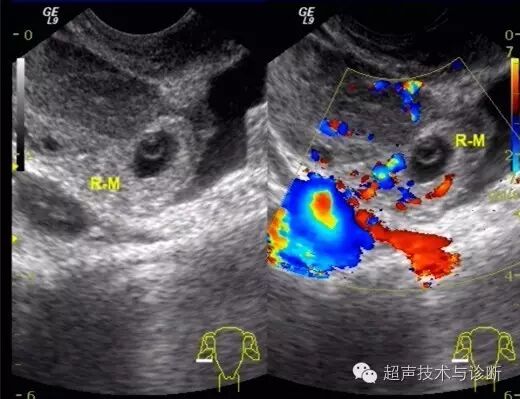

4、超声检查如下(2016。02。01):子宫形态大小正常,宫腔内见一不规则囊性结构,大小4x2cm,透声差,未见双环征及胚芽结构,CDfi未见血流。双侧卵巢可见,右侧附件区可见一囊性结构,大小3x2cm,其内可见胚芽及心管博动。

入院血HCG及超声检查图像如下;